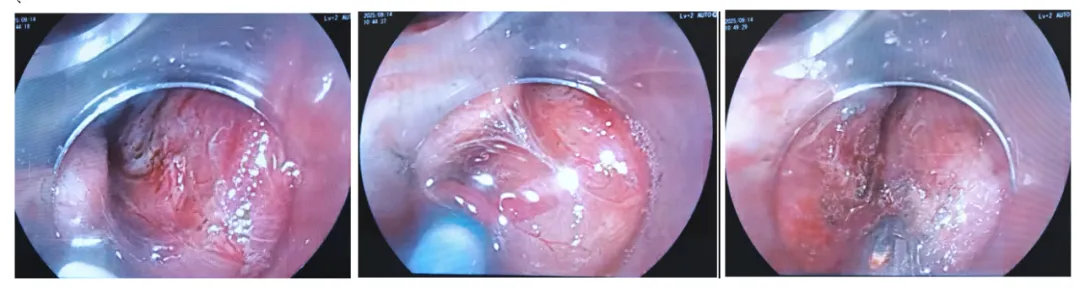

9:38此例选用的是富士3.8mm通道的治疗镜,外径10.5mm,吸引及进出器械好,因镜子粗一些,所以操作灵敏度比细镜会差一点;爱尔博电刀,胃、食管、肠道ESD的电切参数都是3-2-4,电凝是强凝模式2-50W选用的是Dual刀,粘膜下注射的是生理盐水加地塞米松,预防术后狭窄,1mg DXM配1ml NS。个人习惯透明帽伸出3mm左右总体策略尽量保留1/4正常粘膜基础上,尽量完整剥离病灶沿标记点旁粘膜下注射水垫隆起后,先是从1/4正常粘膜边界做切开,然后在肛侧做环形切开再从上向下切开,利用重力因素剥离9:40-45,现在沿肛侧标记点,做切开,再剥离。遇到出血,先止血

9:52现在转到口侧做环形切开粘膜层,因为有心脏搏动,食管收缩,加上镜子粗一些,所以操作空间比较小。

9:58Dual刀粘膜下补水后继续从上往下剥离(有时会换粘膜注射针注射,隆起会比较好一些),粘膜下层非常溥,水垫很快消失。

10:05-14当剥离到困难时,有时也会用牙线或圈套器或“O”型圈内牵引,用“口袋法”自身牵引也可以。有些地方纤维化非常明显,现在是利用重力往下牵引剥离